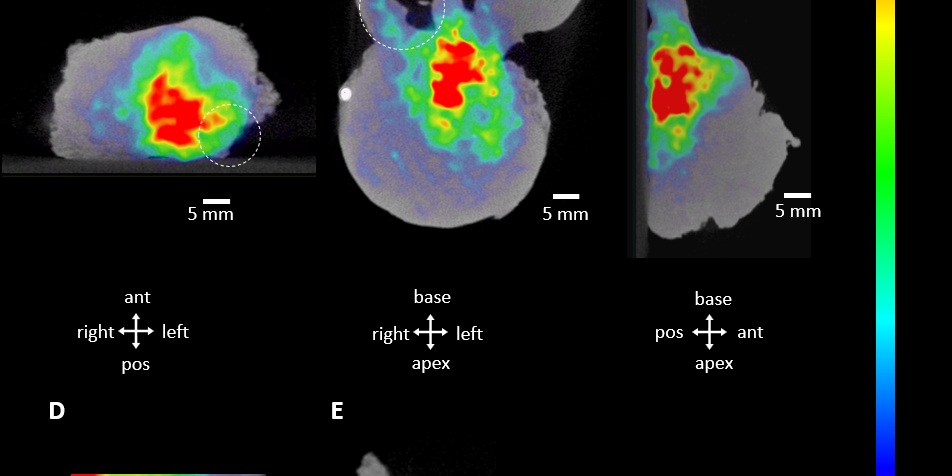

Tässä tapauksessa tarkastellaan, kuinka intraoperatiivinen näytteen PSMA PET-CT auttaa visualisoimaan tuumorin näytekudoksessa. Tämä auttaa kirurgia päättämään, milloin marginaali poistettavan tuumorin osalta on riittävä.

Eturauhassyövän operatiivisessa toimenpiteessä jäädytetyt leikkeet resekoidusta tuumorista ovat edelleen arkipäivää. Intraoperatiivisessa käytössä Aura 10 -laitteisto antaa PSMA kohdennetulla merkkiaineella selkeän kuvan marginaalin arvioimiseksi. Tämä parantaa toimenpiteen onnistumisen mahdollisuuksia, sekä vähentää adjuvanttihoitojen tarvetta.